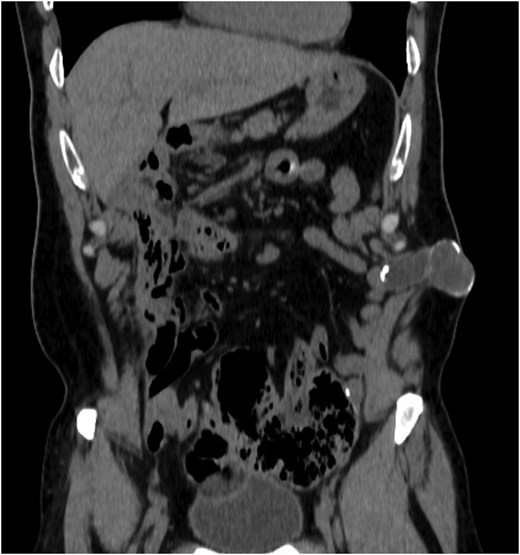

A 52-year-old Caucasian male presented with a palpable mass in the abdominal wall at the site of a previous colostomy. His surgical history included a colostomy performed at 15 months of age due to ileus, followed by restoration of digestive continuity 1 month later, as well as a cholecystectomy in adulthood. The patient was a smoker with no other known comorbidities. Physical examination revealed a firm, well-defined, non-tender mass in the area of the previous stoma. The overlying skin was intact, without signs of inflammation. Laboratory investigations, including tumor markers, were within normal limits. Contrast-enhanced computed tomography (CT) demonstrated a well-encapsulated cystic lesion located above the posterior sheath of the rectus abdominis muscle, without communication with the gastrointestinal tract. No lymphadenopathy or other suspicious findings were observed (Figs 1 and 2).

Coronal perception of CT demonstrating the lesion of the abdominal wall.